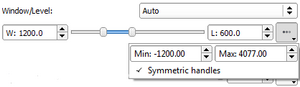

| qMRMLWindowLevelWidget |

|

A widget to set the window level of a vtkMRMLVolumeNode |